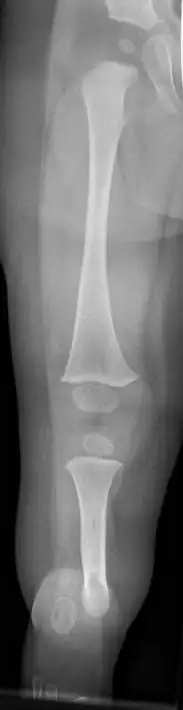

Fibula hemimelia in patient affecting right side | |

Fibular hemimelia or longitudinal fibular deficiency is "the congenital absence of the fibula and it is the most common congenital absence of long bone of the extremities."[1][2] It is the shortening of the fibula at birth, or the complete lack thereof. Fibular hemimelia often causes severe knee instability due to deficiencies of the ligaments. Severe forms of fibula hemimelia can result in a malformed ankle with limited motion and stability. Fusion or absence of two or more toes are also common.[3] In humans, the disorder can be noted by ultrasound in utero to prepare for amputation after birth or complex bone-lengthening surgery. The amputation usually occurs at six months with removal of portions of the legs to prepare them for prosthetic use. The other treatments, which include repeated corrective osteotomies and leg-lengthening surgery (Ilizarov apparatus), are costly and associated with residual deformity.[4]